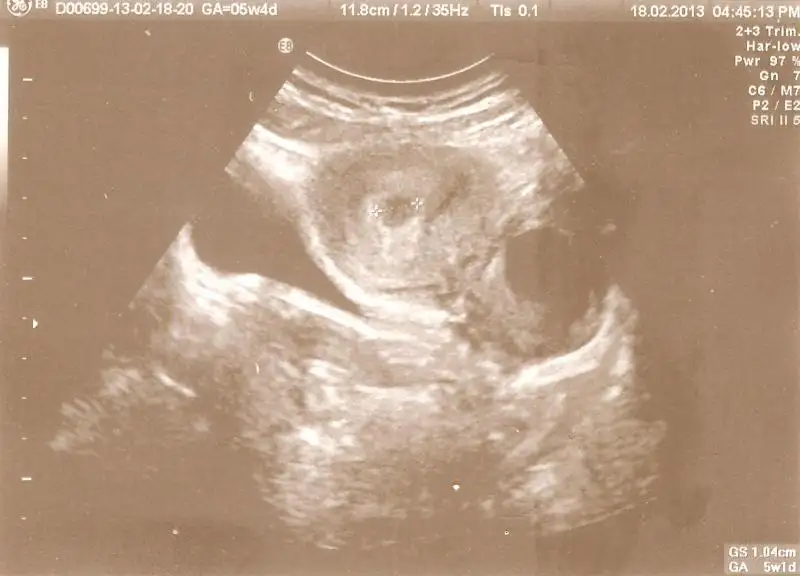

dünkü kesemin ultrason görüntüsünü sizler için taradım kızlarselam kızlar

dünkü kesemin ultrason görüntüsünü sizler için taradım kızlar

veri olarak dursun

miniğim 5hafta 4 günlükmüş